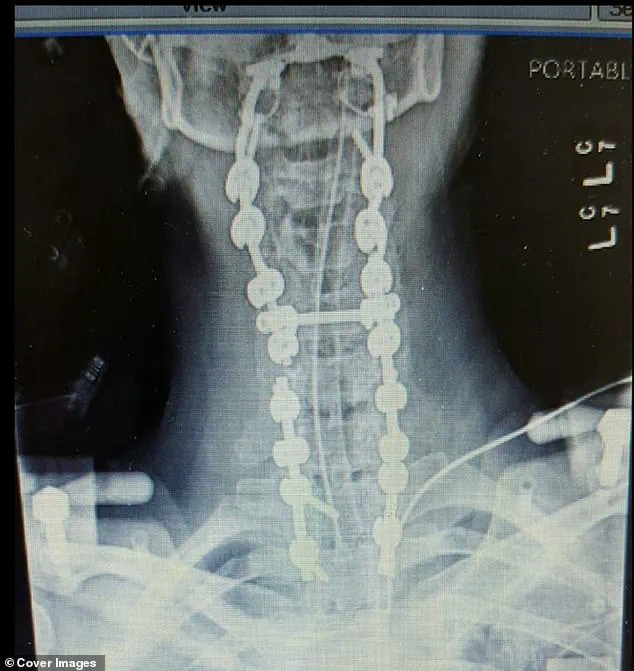

Today, Megan’s body is fused from her skull down to her pelvis in an effort to ensure her spine remains stable and prevent any more dangerous dislocations.

A spinal fusion procedure involves joining two or more vertebrae together so that they become solid bone, effectively eliminating movement between those segments of the spine.

Following this harrowing incident, King underwent extensive surgical procedures to fuse her neck and spine from her skull down to her pelvis.

The images showcasing these fusions illustrate the extent of her medical journey—a fusion that ensures her spinal column remains stable but restricts any bending or twisting movements.